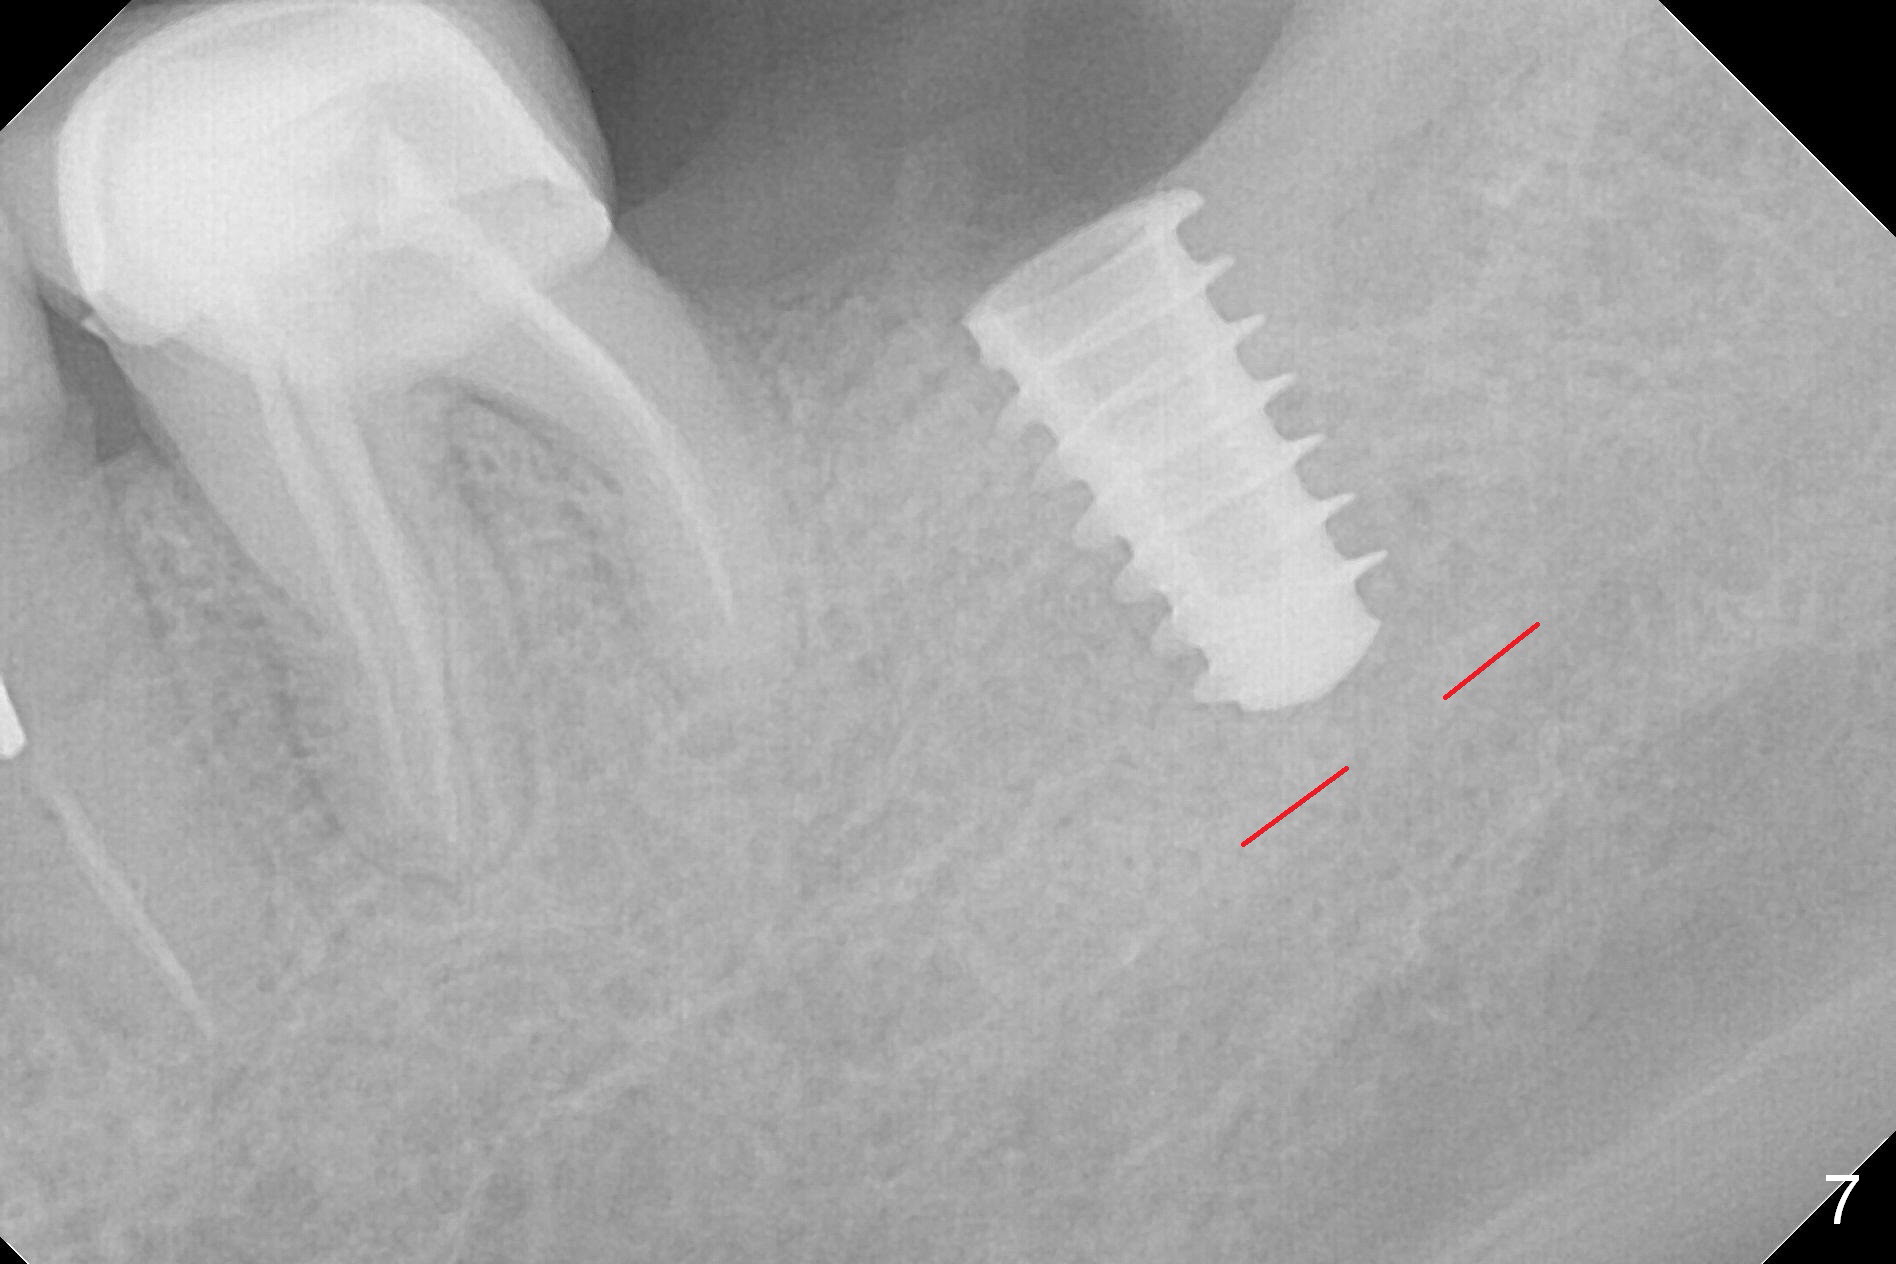

After 1.6 mm pilot drill (Fig.2) and 4.3 mm Magic Drill for 11 mm (gingival margin), a 4.5x11 mm dummy implant is placed with stability (Fig.3). Following Final Drill for 12/13 mm and 4.3 mm MD mesially, a 5x9 mm IBS implant is placed with 40 Ncm (Fig.4). Panoramic X-ray shows the placement is slightly supracrestal (Fig.5). In fact the implant is also placed slightly lingually. When the trajectory is changed, the implant loses stability. When a 5.5x9 mm implant is placed, no stability is achieved (Fig.6). After increase in osteotomy depth for 1-2 mm with MD 4.3 mm, the 5.5x9 mm implant barely obtains stability (~ 10 Ncm, Fig.7). Healing screw is placed. Osteogen plug is inserted in the distal portion of the socket; autogenous bone around the implant and Collagen plug to close the socket opening. Last suture and periodontal dressing are applied.

In fact, the mesial crest of the socket could be used as a more secure landmark (bony vs. soft tissue) for osteotomy depth (Fig.4 arrowhead) with drill stopper. To place the implant subcrestal, the initial osteotomy should be 1-2 mm deeper. When she returns 2 years 9 months postop, the wound has healed. The implant needs to be uncovered. Make sure to have clearance for a healing abutment. Use sensor 1 for PAs before and after uncover. The implant appears to be tilted distal. An angled abutment may be required. Take PA for seating confirmation. Guided surgery is preferable. The implant plateau is covered by the bone 2 years 9 months postop (Fig.8 *). The healing screw is removed with difficulty, while a 6x3 mm healing abutment is placed with resistance, probably related to interference from the distal crest (Fig.9 *). It is much easier with removal of the crest bone using surgical bur, because of clearance (Fig.10 *). It is the best to have a particular drill to remove the excess bone. There is no interference to insert and torque a 5x4(2) mm pair abutment 2 weeks post uncover (Fig.11). Due to poor trajectory (guide necessity) and tight proximal contact, the crown is not completely seated (Fig.12). However, the abutment screw is unlikely to get loose in the future.